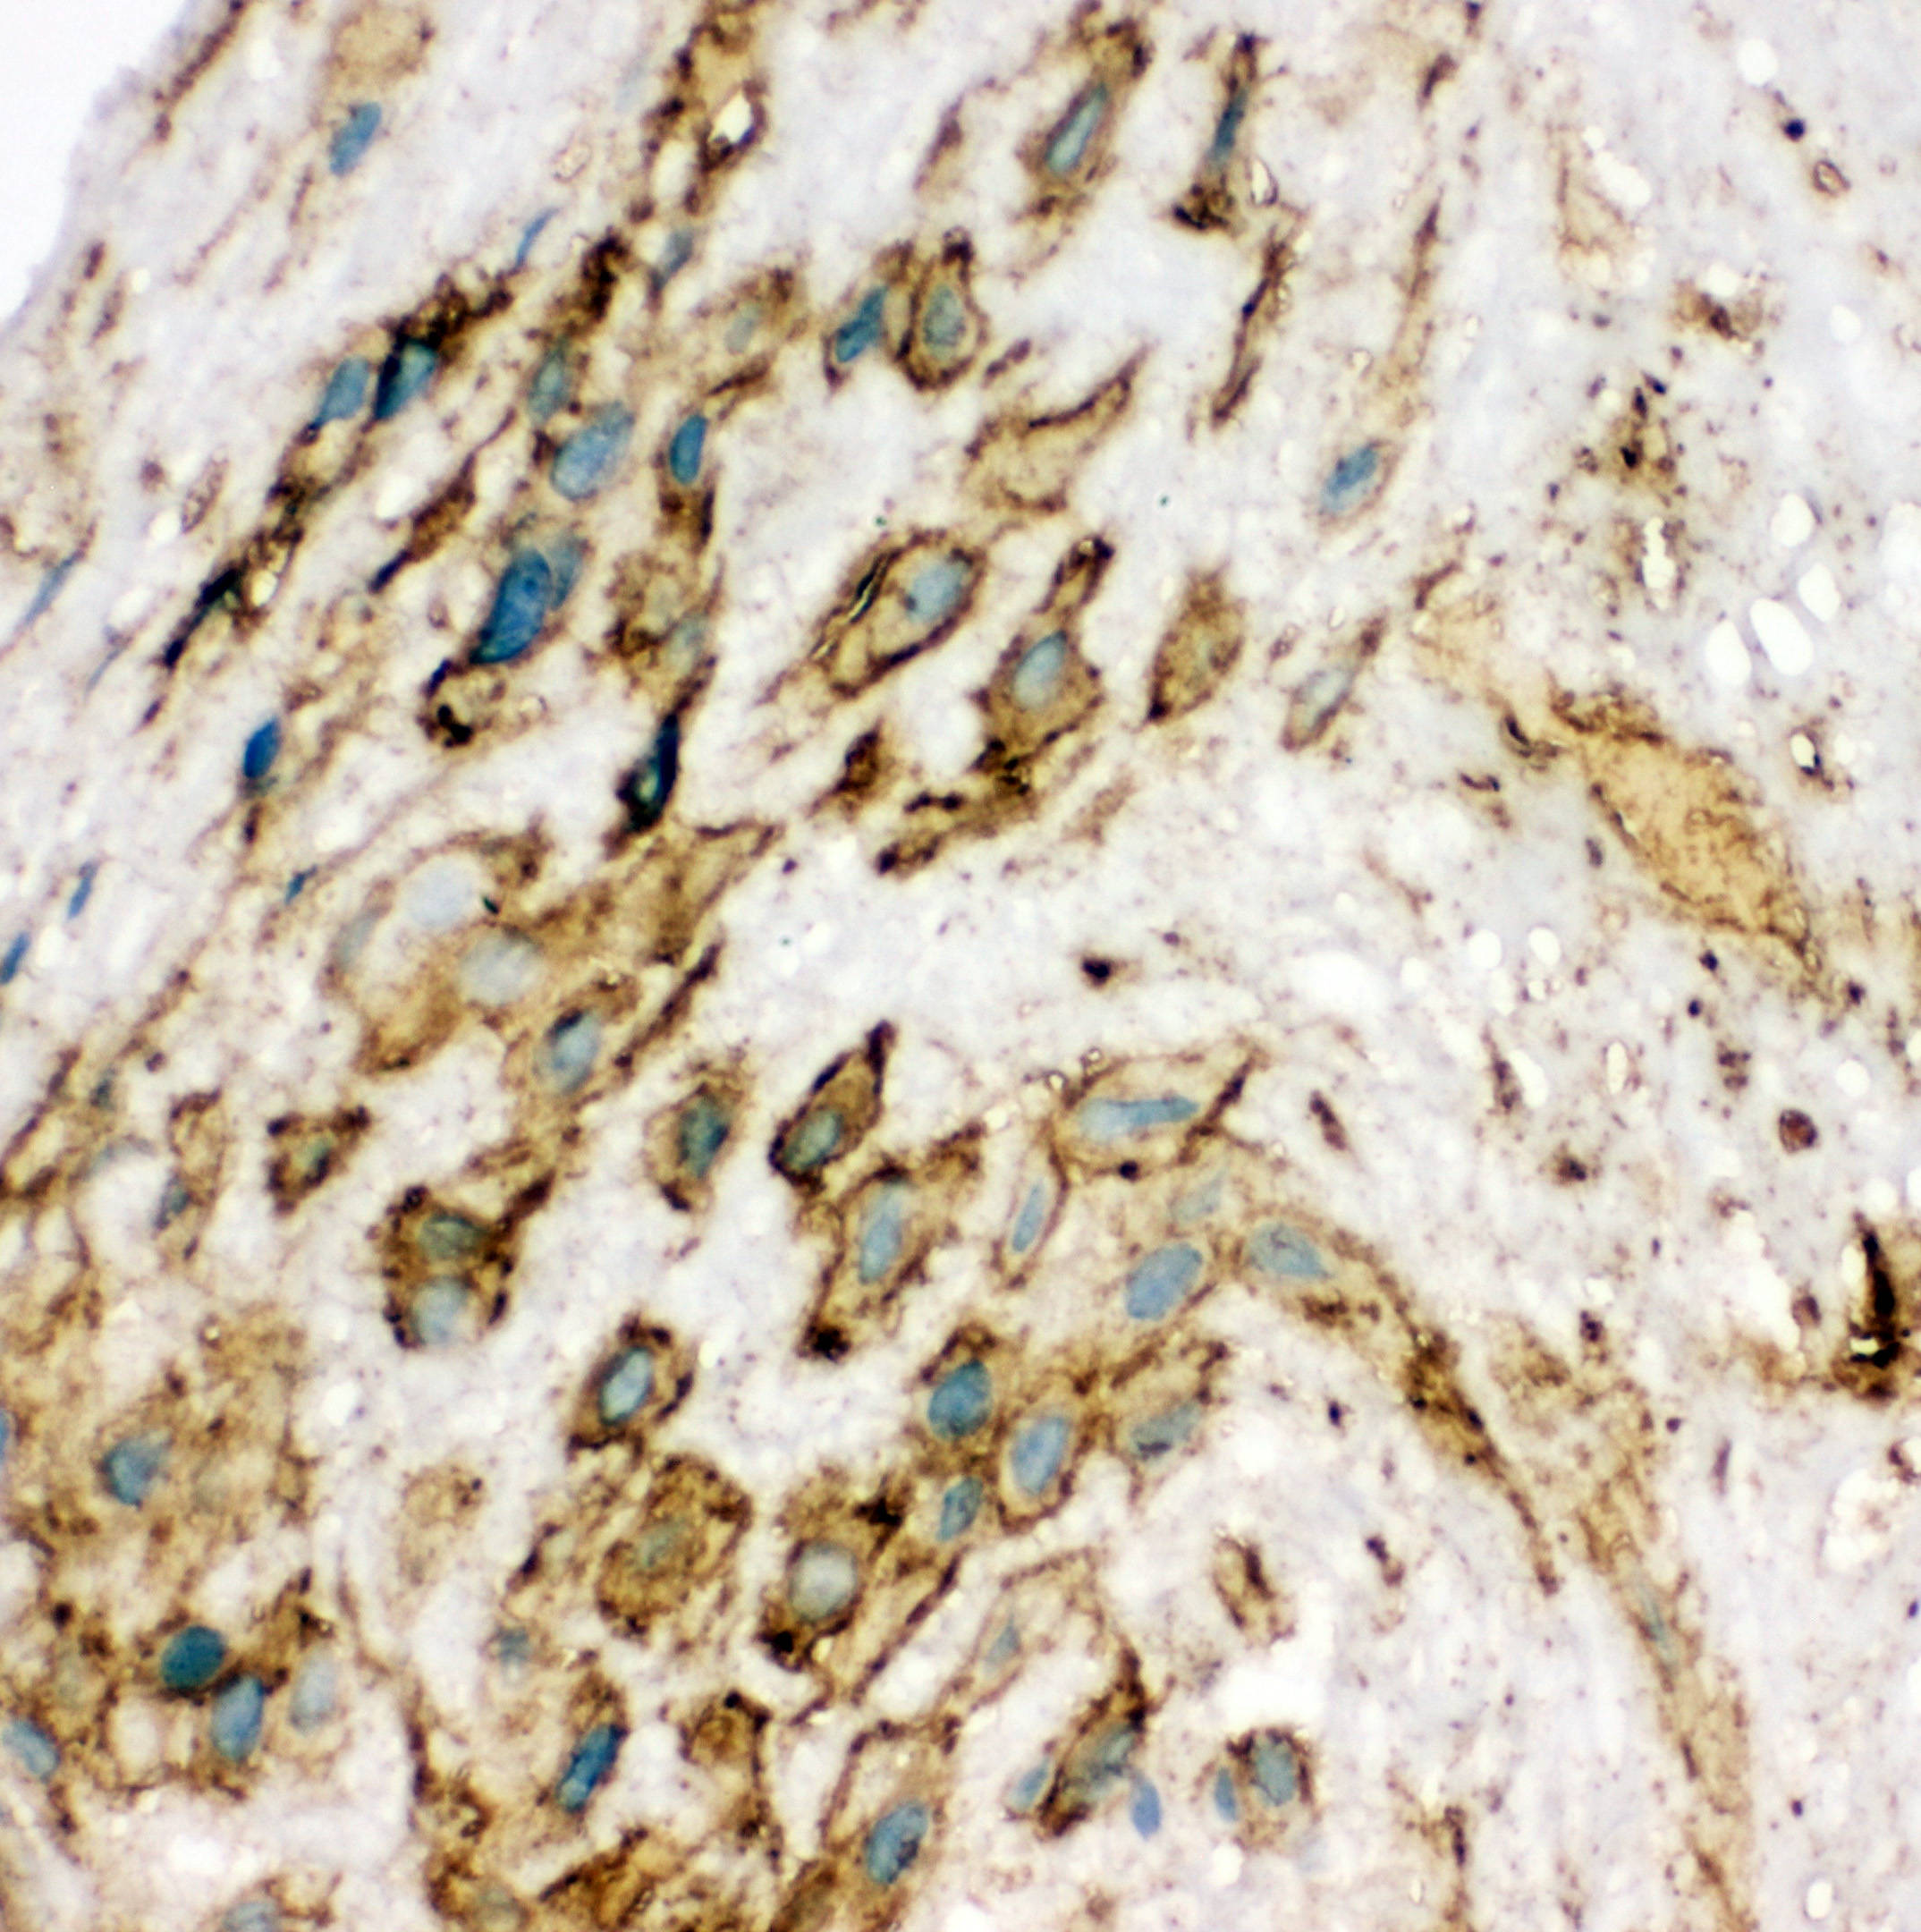

IHC analysis of VEGFR2/KDR using anti-VEGFR2/KDR antibody (BA0472).

VEGFR2/KDR was detected in frozen section of human placenta tissue. The tissue section was incubated with rabbit anti-VEGFR2/KDR Antibody (BA0472) at a dilution of 1:200 and developed using HRP Conjugated Rabbit IgG Super Vision Assay Kit (Catalog # SV0002) with DAB (Catalog # AR1027) as the chromogen.